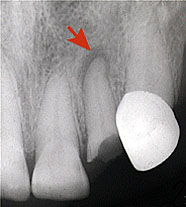

Хронический гранулирующий периодонтит до лечения

Хронический гранулирующий периодонтит до лечения.